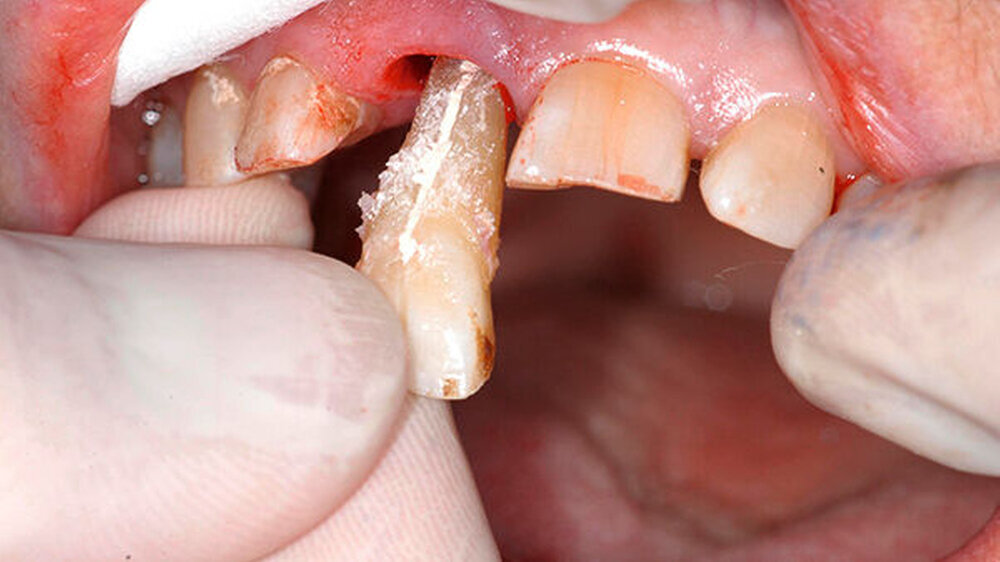

Anschließend erfolgte die Extraktion des Zahns unter weitestgehender Schonung der umgebenden Hart- und Weichgewebe. Zur Vitalerhaltung der parodontalen Ligamentzellen wurde Zahn 11 direkt nach Extraktion in einem Zellnährmedium (Zahnrettungsbox; Medice Pharma, Iserlohn, Deutschland) gelagert.

Während die palatinale Fläche unbeschädigt war, zeigte die bukkale Fläche eine vertikale Frakturlinie (Abbildung 3), die mit einem feinen diamantierten Schleifkörper erweitert wurde (Abbildung 4). Zusätzlich erfolgte die Entfernung des retrograden Wurzelkanalfüllmaterials. Beide Defekte wurden mit Biodentine (Septodont, Niederkassel) aufgefüllt (Abbildung 5).